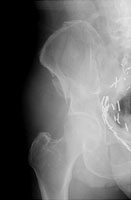

Duverney fractures are stable pelvic injuries. The fracture consists of an isolated fracture of one iliac wing. The pelvic ring remains intact although the patient is at risk for hemorrhage from the internal iliac arterial system. These fractures are caused by vertically directed forces.

- Click on the image for a larger versionBAP radiograph of the right hip. The fracture lines are better seen. This patient fell.